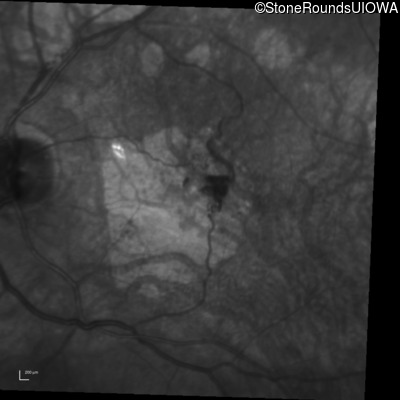

Infrared Fundus Photograph - Right - 20/125 -2

Exemplar